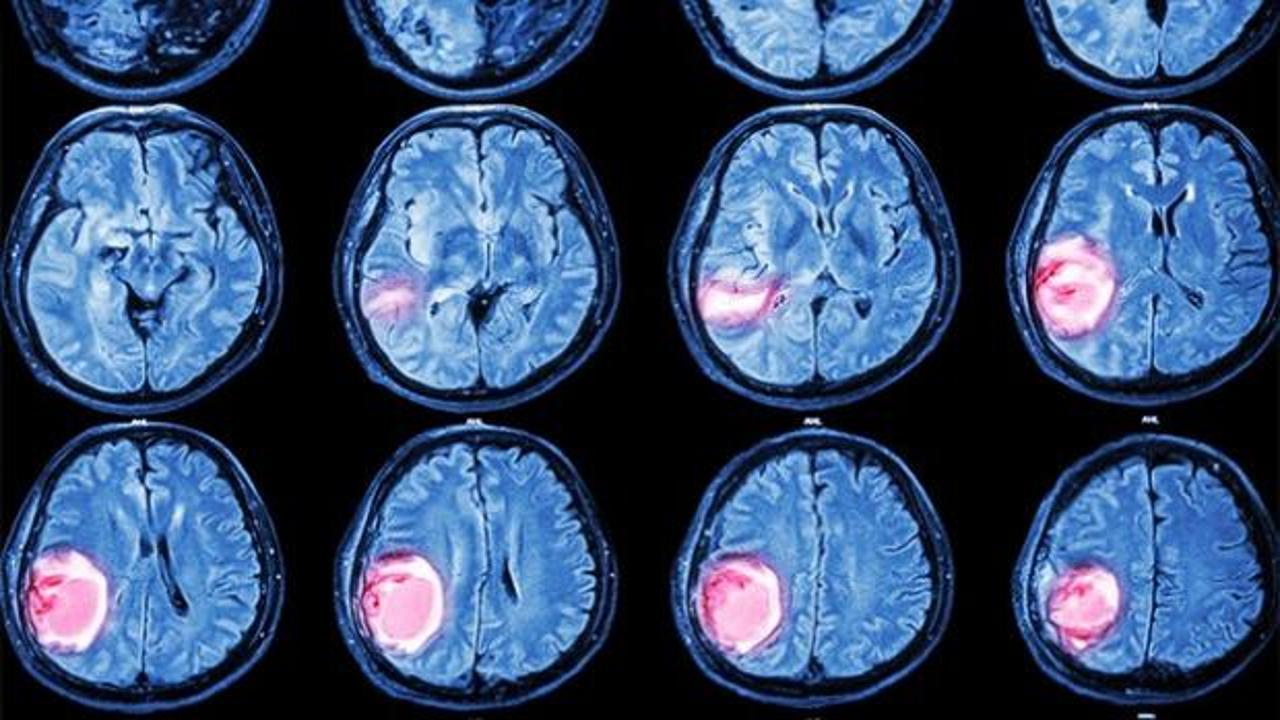

Beyin tümörleri, beynin kendisinden, etrafındaki zarlardan veya kafatasından kaynaklanabildiği gibi vücudun başka bölgelerindeki kanserlerin beyne yayılmasıyla da oluşabiliyor.

Beyin tümörlerinin belirtilerini sıralayan Dr. Gökçek, “Bulantı, kusma, baş ağrısı, baş dönmesi, sara nöbetleri, kişilik değişiklikleri, hafıza ve görme bozuklukları, anormal göz hareketleri ve kulakta çınlama beyin tümörlerinin en sık görülen belirtileri arasında” dedi. Beyin tümörlerinin kesin tanısı için MR çekiminin altını çizen Dr. Gökçek, “Kapalı alan korkusu olan hastalar için tomografi kısa sürede bilgi verebilir. Ancak beyin tümörlerinin doğru şekilde tespiti ve lokalizasyonu için MR şarttır” diye konuştu.